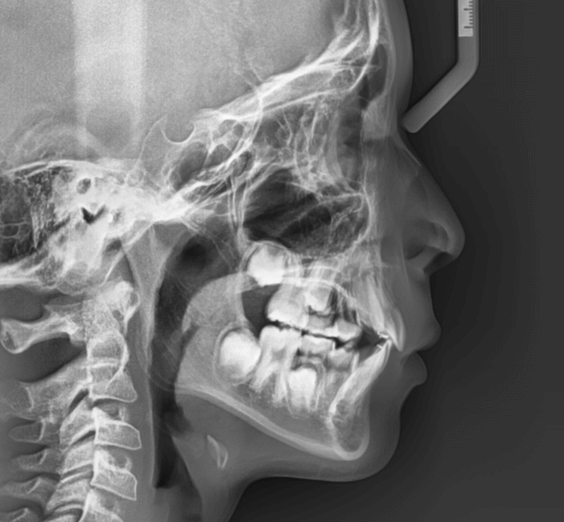

| 年齢・性別 | 11歳1ヶ月の女性 |

|---|---|

| 主訴 | 口元の突出感と歯並びが気になり、将来的な咬合状態を整える目的で来院された患者様です。 |

| 治療期間・回数 | 2年6ヶ月・25回 |

| 費用 | 720,000円 |